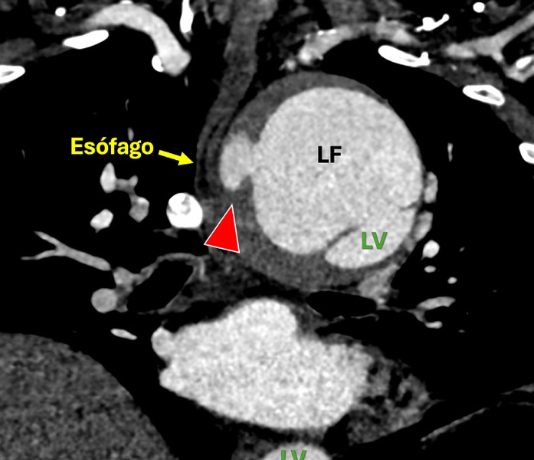

Paciente masculino de 57 años se presentó con dolor torácico interescapular de inicio abrupto. Ocho años antes, debido a una disección aórtica tipo A, fue sometido a un reemplazo de aorta ascendente y hemiarco -con reimplantación del tronco braquicefálico y la arteria carótida común izquierda- con seguimiento irregular. La angio-TC mostró un aneurisma toracoabdominal tipo II con una dilatación de la aorta torácica de 8 cm, asociado a “pool” sanguíneo intramural1 que emergía desde el lumen falso en dirección y estrecha relación con el esófago (Figura 1 y 2).